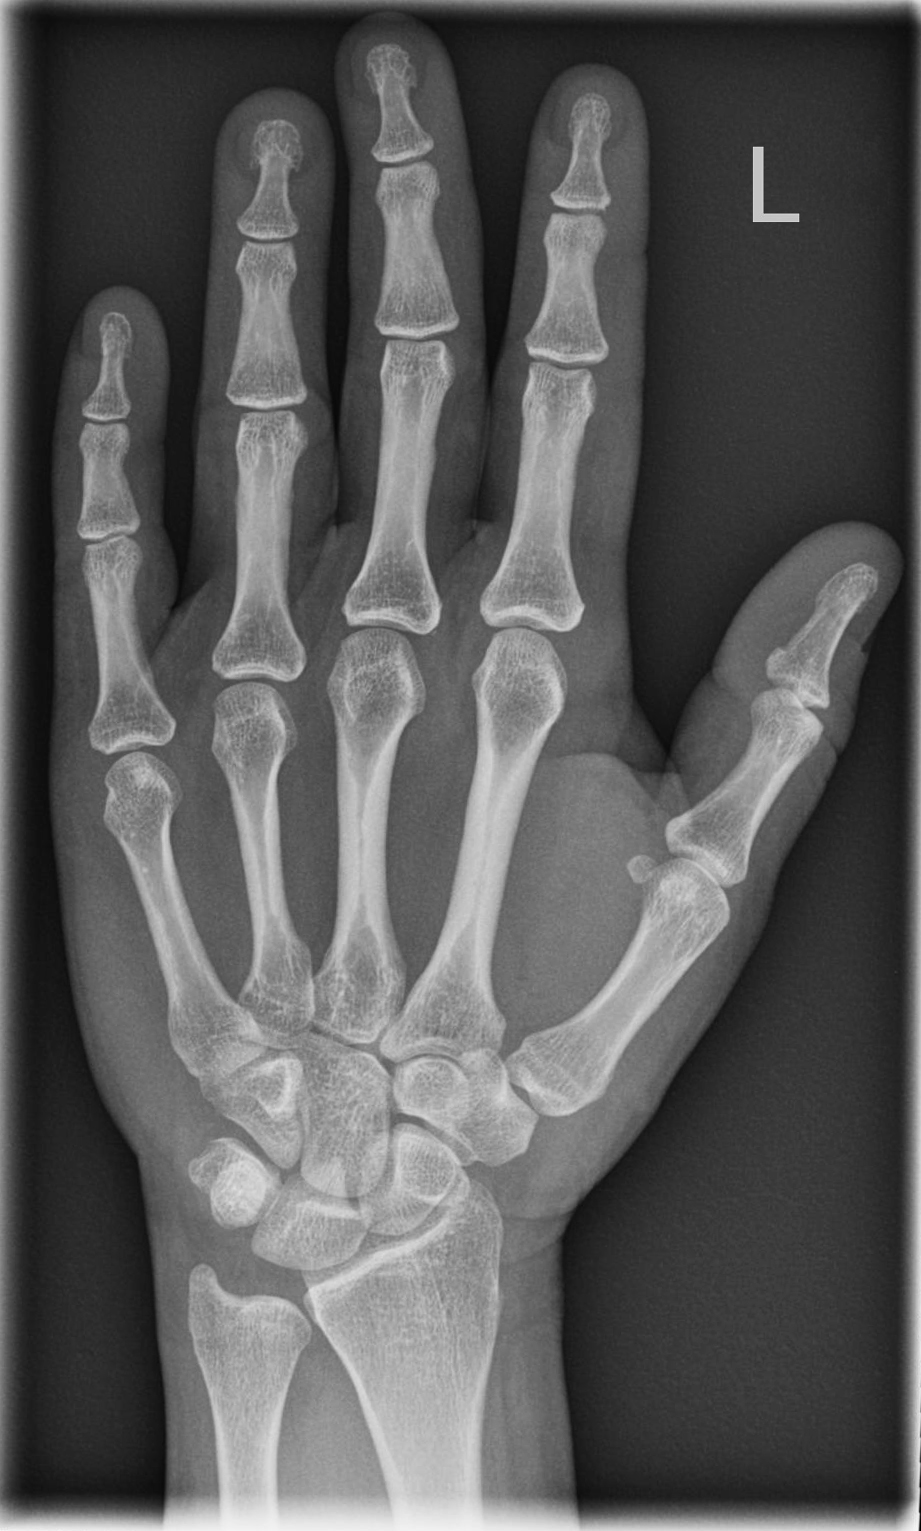

Hand d.v. (dorso-volar)

Indikation

Frakturen, entzündliche (Arthrose) und degenerative Veränderungen (Arthritis), chronische Polyarthritis (Rheuma)

Patient sitzt seitlich zum Tisch, Beine befinden sich neben Tisch abgewinkelter Unterarm und die Handfläche liegen auf.

Übersichtsdarstellung des Skeletts bei Frakturen, Arthrosis und Deformierung der Gelenke, sowie chronischer Polyarthritis (Rheuma).

Qualitätskriterien

vollständige Darstellung der ganzen Hand inklusive Handgelenk, Buchstabe